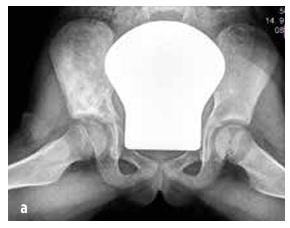

Din punct de vedere osos, cele mai frecvent afectate sunt metafizele oaselor lungi, clavicula, corpurile vertebrale și pelvisul (vezi imaginea nr. 2). Numărul leziunilor osoase este variabil (uneori doar un singur focar, mai frecvent multiple). Uneori, leziunile asimptomatice sunt detectate prin scintigrafie osoasă sau rezonanță magnetică totală (WB MRI).

Imaginea nr. 2

Comparație între distribuția leziunilor osoase la RMN la copii cu CRMO și cu osteomielită septică (conform Schnabel et al., 2016)